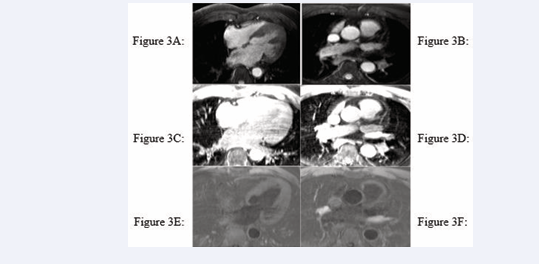

All cardiac chambers and great vessels were quantitatively analysed for CNR and SNR using Osirix software. Regions of interest (ROIs) were defined to determine the signal (S) from blood (SBlood ) in the left ventricle (LV), right ventricle (RV), pulmonary artery (PA), ascending and descending aorta (Ao), and pulmonary veins (PV) relative to the reference tissue (SMyocardium ). Noise (N) was estimated according to the standard deviation of these respective ROIs. CNR was defined by using the following equation: CNR = (SBlood -SMyocardium )/(0.5 × [NBlood +NMyocardium ]), where all variables are mean values. SNR was defined using the equation SNR = (SBlood )/(NBlood ) [9]. Image processing and reformatting were performed with commercially available analysis software (View Forum; Philips Healthcare).The image gradient system was modified based on McConnell et al [20] (Figure 2). Consensus reading was performed for image quality scoring by two readers using the image quality scores defined in Table 2. The readers analysed all images independently in a blinded and random order. Disagreements were discussed before a single final grade was given. Visual inspection was performed to identify the intracardiac and extracardiac arterial and venous structures [21] (Figures 1, 2 and 3).

Identification of intracardiac and extracardiac arterial and venous structure

Figure 1: Identification of intracardiac and extracardiac arterial and venous structure

Identification of intracardiac and extracardiac arterial and venous structures

Figure 2: Identification of intracardiac and extracardiac arterial and venous structures

Figure 3: Identification of intracardiac and extracardiac arterial and venous structures